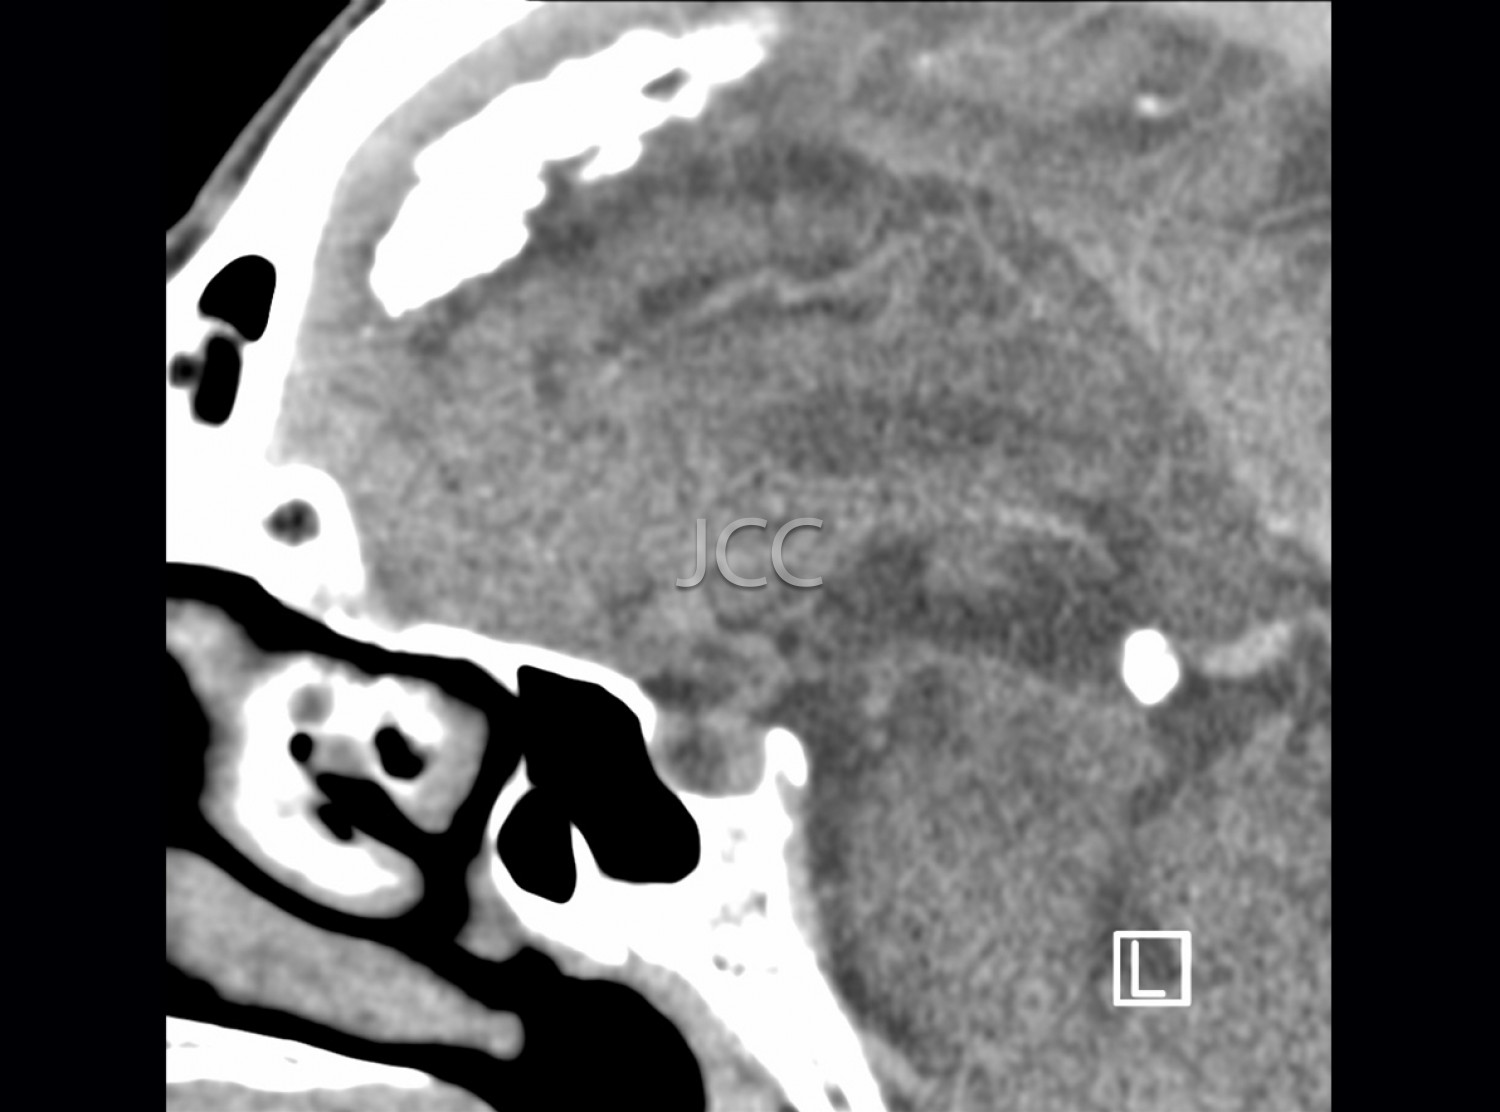

Computed Axial Tomography - Pituitary CAT scan

Computed Axial Tomography (CAT) - Dual Energy - 256 slices is a diagnostic technique that allows the evaluation of various parts of the human body, including the lungs, liver, pancreas, kidneys, heart, vascular structures and bone structures.